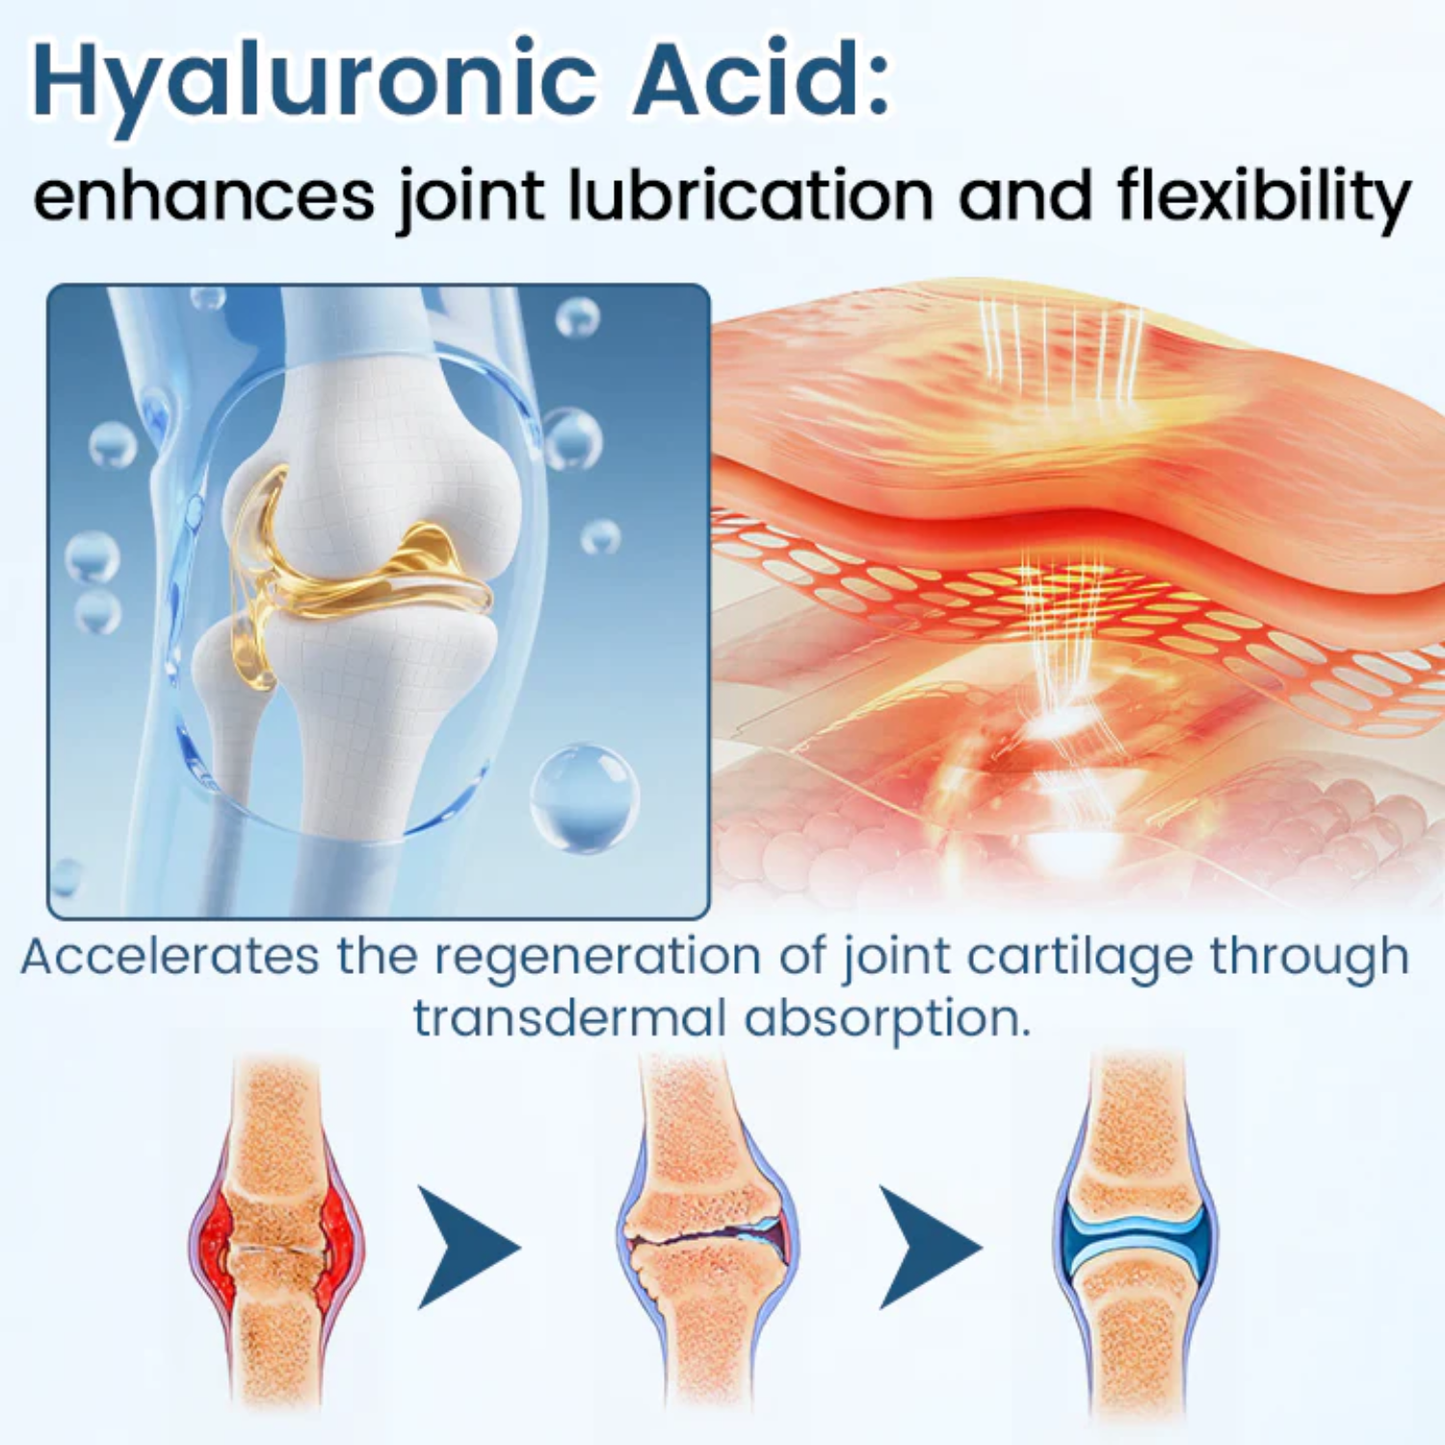

Hyaluronic Acid – Joint Lubrication and Flexibility

Hyaluronic Acid replenishes natural synovial fluid in the joints, reducing friction between bones and restoring smooth movement. It deeply hydrates tissues, improves elasticity, and enhances the absorption of BPC-157, allowing faster cartilage repair and long-lasting joint protection.